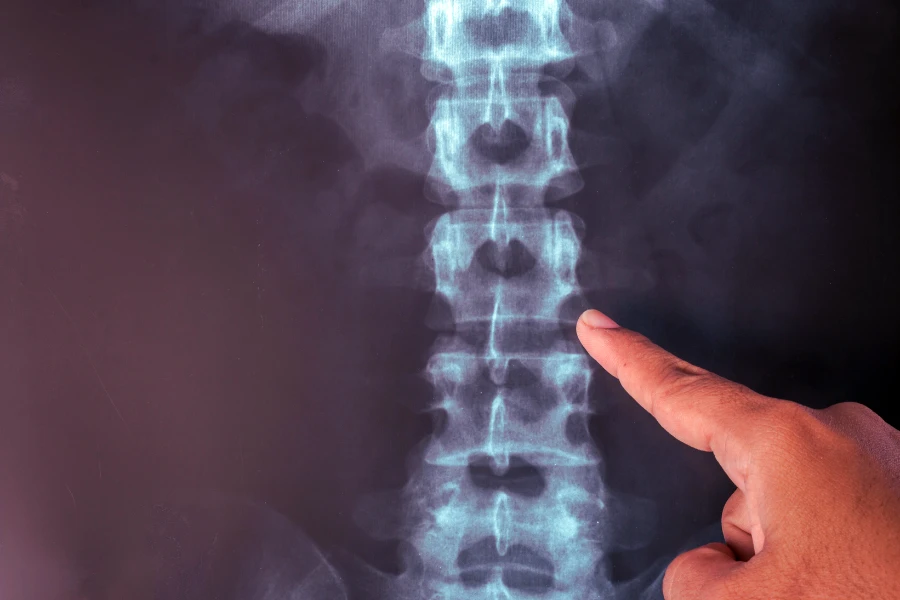

Діагностика метастазів у хребті базується на комплексному підході, який поєднує клінічний огляд, інструментальні методи візуалізації та лабораторні аналізи. Першим етапом є детальний збір анамнезу з уточненням наявних онкологічних захворювань, характеру болю в спині, неврологічних симптомів та темпів їх прогресування. Лікар проводить неврологічний огляд, оцінює силу м’язів, чутливість, рефлекси та можливі прояви здавлення спинного мозку.

Найбільш інформативним методом діагностики вважається МРТ хребта, оскільки саме цей вид дослідження з високою точністю відображає стан як кісткових структур, так і м’яких тканин, включно зі спинним мозком. При проведенні магнітно-резонансної томографії лікар може побачити навіть найменші зміни у кістковому мозку, які часто є першими ознаками метастатичного ураження, а також може визначити точну локалізацію, розміри та кількість пухлинних вогнищ. Це дослідження показує ступінь руйнування хребців, наявність компресійних переломів, поширення метастазів у паравертебральні тканини, епідуральний простір або міжхребцеві отвори.

МРТ дозволяє виявити здавлення спинного мозку, набряк, порушення його структури та компресію нервових корінців, що є критично важливим для своєчасного запобігання паралічу й тяжким неврологічним ускладненням. На відміну від рентгена чи комп’ютерної томографії, МРТ чітко відображає м’які тканинні компоненти пухлини, судинні структури та ступінь проростання у навколишні анатомічні області, що робить обстеження незамінним для діагностики метастазів.